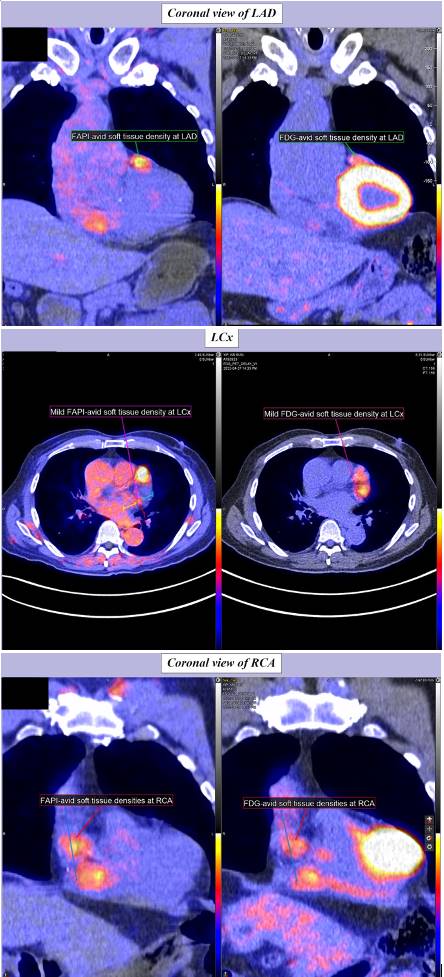

The patient was a 74-year-old Chinese male who presented with left hemiparesis due to intra-cranial haemorrhage in the right thalamus. He had history of hepatitis B carrier status, bronchiectasis and hyperlipidaemia. He was referred for echocardiogram, which showed a large solid-looking “tumour” mass (2.2 × 2.3 cm) in the right atrioventricular groove with mass effect (Figure 1). Magnetic Resonance Imaging scan of the heart showed a concentric mural lesion (measuring 3.2 × 2 × 2.3 cm) encasing the mid-to-distal right coronary artery (RCA) and a similar but smaller concentric mural lesion encasing the mid-left anterior descending artery (LAD). Computed tomography (CT) coronary angiogram showed non-obstructive coronary artery disease with multiple segments of concentric mural thickening around the RCA, LAD, diagonal artery and left circumflex artery (LCx), compatible with coronary arteritis. The largest lesion at mid-distal RCA had the appearance of a “pig-in-a-blanket” (Figure 2). Serum IgG4 level was grossly elevated at 9.85 g/L (normal range 0.04 - 0.86 g/L). The diagnosis of IgG4 coronary arteritis was made. Further assessment of the extent of the disease was performed by PET/CT scan with 18F-fluoro-deoxy-glucose (FDG) and 68Ga-Fibroblast Activation Protein Inhibitor (FAPI) tracers. PET/CT demonstrated mild 18F-FDG and 68Ga-FAPI activity at the soft tissue densities along the LAD, RCA and LCx, suggestive of inflammation along the coronary arteries (Figure 3). A small 68Ga-FAPI-avid focus at pancreatic head, suggestive of same disease involvement, was not detectable by 18F-FDG scan. While the 18F-FDG scan showed mild grade activity along the ascending and descending thoracic aorta and lymph nodes (non-specific findings), activity was not detectable on the 68Ga-FAPI scan. Bone marrow aspirate was normal and did not show any increase in plasma cells. Despite the lack of symptoms, treatment was indicated to prevent the progression of IgG4-RD in the heart and other major organs. In view of his hepatitis B carrier status, it was decided not to give him glucocorticoid therapy. He was given 8 doses of intravenous rituximab (an anti-CD20 antibody) at 375 mg/m2 weekly for 4 doses followed by 375 mg/m2 once every 2 months for 4 more doses with good serological response (Figure 4). He had good recovery from his stroke and remained free from any cardiac symptoms. Repeat CT coronary angiogram after the rituximab therapy showed similar mural thickening around the coronary arteries with no change in the size of the largest pseudo-tumour around the RCA.

Figure 3. Corresponding 68Ga-FAPI PET/CT scan images (left hand side) and 18F-FDG PET/CT scan images (right hand side) of the three coronary arteries: left anterior descending artery (LAD), left circumflex (LCx) and right coronary artery (RCA).

Traditionally 18F-FDG positron emission tomography/computed tomography (PET/CT) is used to assess the extent of inflammation in IgG4-RD and to monitor disease activity after treatment. 18F-FDG PET/CT had a sensitivity of 85.7% and specificity of 66.1% for diagnosing IgG4-RD. However, false-negative finding of 18F-FDG PET was also noted in some studies [10] [11]. In IgG4-RD, fibrosis produced by the large number of fibroblasts is a major histopathologic feature. Therefore, a recently introduced PET agent targeting fibroblast activation protein, 68Ga-fibroblast activation protein inhibitor (68Ga-FAPI), has been used to assess IgG4-RD. Unlike 18F-FDG which accumulates in cancer cells and active inflammatory lesions, 68Ga-FAPI uptake is associated with the degree of fibrosis and is more specific for IgG4-RD. There is evidence that 68Ga-FAPI PET/CT had a higher positive rate than 18F-FDG PET/CT in the detection of IgG4-RD in the pancreas, bile duct/liver, and salivary gland [12]. In our patient, although both 18F-FDG and 68Ga-FAPI PET/CT showed involvement of the coronary arteritis, there were differences in tracer uptake in other organs. There was non-specific FDG uptake in the aorta and lymph nodes which were not 68Ga-FAPI avid while a small 68Ga-FAPI-avid focus at pancreatic head was not detectable on the 18F-FDG scan. Even though pancreas is a common organ to be involved in IgG4-RD, the clinical significance of this small 68Ga-FAPI-avid focus remained unclear.